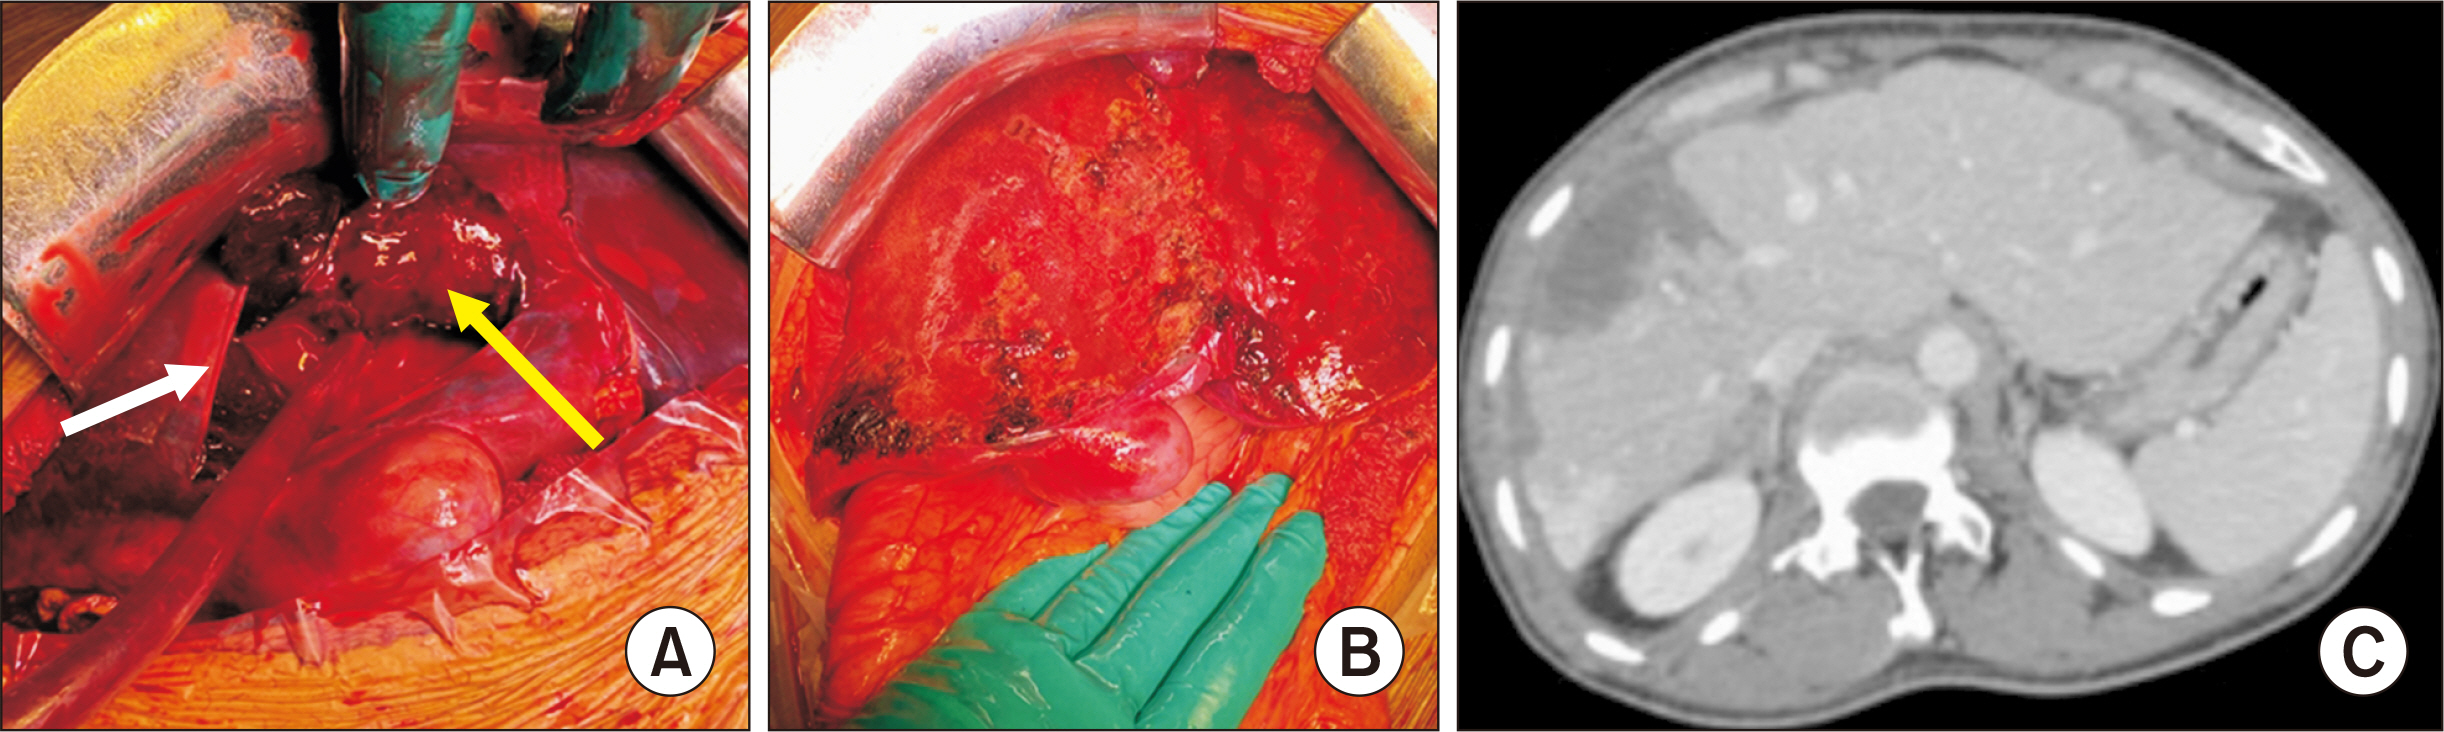

- Hepatic compartment syndrome (HCS) is a rare but life-threatening entity that consists of a decreased portal flow due to intraparenchymal hypertension secondary to subcapsular liver hematoma. Lethal liver failure can be observed. We report three cases, and review the literature. A 54-year-old male was admitted for extensive hepatic subcapsular hematoma after blunt abdominal trauma. Initially, he underwent embolization of the hepatic artery’s right branch, after which he presented clinical deterioration, major cytolysis (310 times the upper limit of normal [ULN]), and liver failure with a prothrombin time (PT) at 31.0%. A 56-year-old male underwent liver transplantation for acute alcoholic hepatitis. On postoperative day 2, he presented a hemorrhagic shock associated with deterioration of liver function (cytolysis 21 ULN, PT 39.0%) due to extensive hepatic subcapsular hematoma. A 59-year-old male presented a hepatic subcapsular hematoma five days after a cholecystectomy, revealed by abdominal pain with liver dysfunction (cytolysis 10 ULN, PT 63.0%). All patients ultimately underwent urgent surgery for liver capsule excision, hematoma evacuation, and liver packing, if needed. The international literature was screened for this entity. These three patients’ outcomes were favorable, and all were alive at postoperative day 90. The literature review found 15 reported cases. HCS can occur after any direct or indirect liver trauma. Surgical decompression is the main treatment, and there is probably no place for arterial embolization, which may increase the risk of liver necrosis. A 13.3% mortality rate is reported. HCS is a rare complication of subcapsular liver hematoma that compresses the liver parenchyma, and leads to liver failure. Urgent surgical decompression is needed.